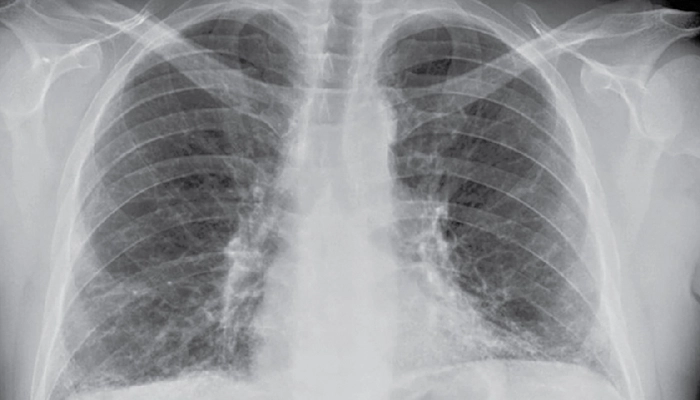

X-quang phổi: Hình ảnh mờ, lưới lan tỏa, không rõ ràng bằng HRCT.

Xquang ngực cho thấy hình ảnh tổn thương kẽ dạng lưới